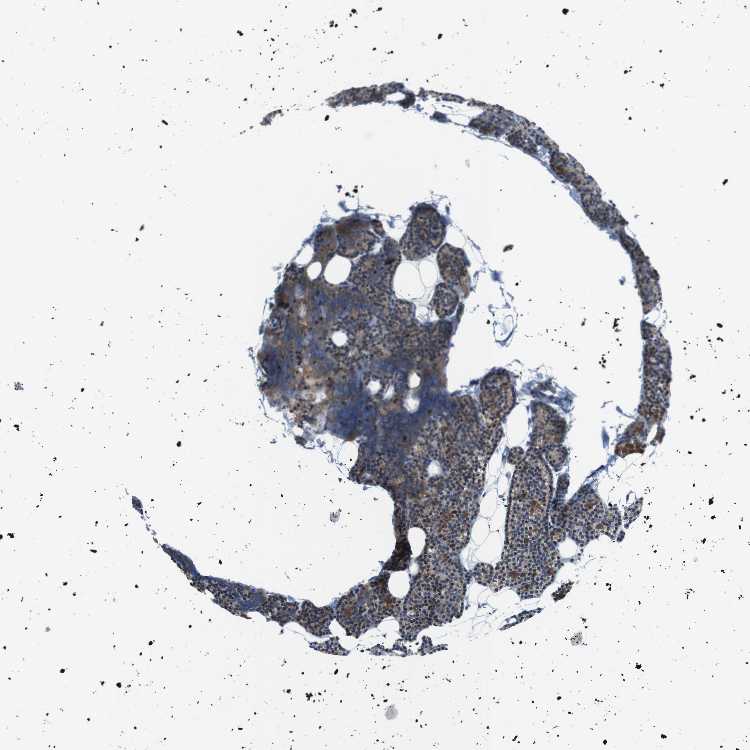

PARATHYROID GLAND - Antibody stainingi

Antibody staining in the annotated cell types in the current human tissue is reported as not detected, low, medium, or high, based on conventional immunohistochemistry profiling in selected tissues. This score is based on the combination of the staining intensity and fraction of stained cells.

Each image is clickable and will lead to virtual microscopy that enables deeper exploration of all samples and also displays staining intensity scores, fraction scores and subcellular localization as well as patient and tissue information for each sample.

Antibody HPA015696Antibody HPA017343

Glandular cells MediumHigh